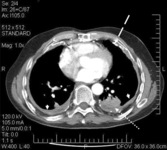

CT scan of the chest showing multiple examples of pleural thickening most with calcification (arrows)

From the personal collection of Kenneth D. Rosenman MD

CT scan confirming symmetrical thickening (arrowheads) with a calcified pleural plaque (broken arrow, top right) and an area of rounded atelectasis (Blesovsky's sign; dotted arrow, bottom right)

Adapted from BMJ Case Reports 2009; doi:10.1136/bcr.06.2008.0253